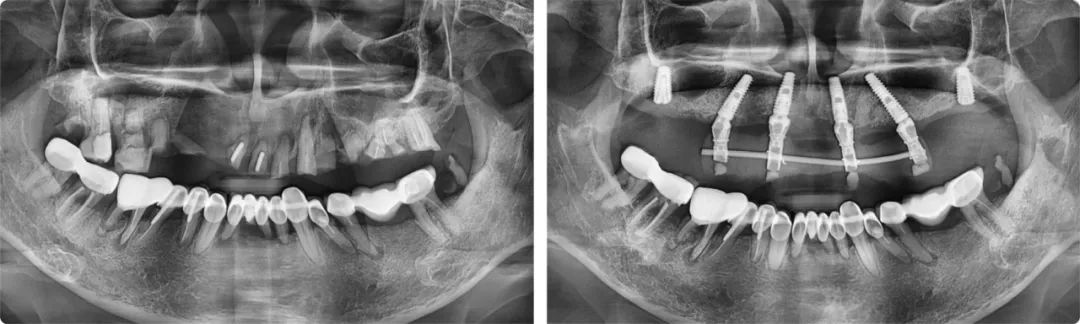

今年五月,葉宏接診了一位56歲的患者。這位患者的上半口全是牙齒殘根,骨量也不好,種植點(diǎn)位非常難選。一般情況下,上頜骨有6-8毫米的高度就可以滿足種植條件,但患者只有2-3毫米,風(fēng)險(xiǎn)較大,且種植位置靠近上頜竇,需要采用斜行植體,穿過兩個(gè)牙位,備孔時(shí)要斜著鉆,非常考驗(yàn)醫(yī)生的技術(shù)水平和臨床經(jīng)驗(yàn)。

為力求最佳的治療效果,葉宏為患者制訂了個(gè)性化的治療方案。“這例上半口種植由于情況特殊,不能一次性完成六顆牙的種植,我分了兩步完成。第一步是即拔即種,種4顆,然后清創(chuàng),等待恢復(fù),三個(gè)月后完成第二步,補(bǔ)種兩顆。”

患者術(shù)前術(shù)后全景片

葉宏解釋了這樣做的原因:標(biāo)準(zhǔn)的無牙頜種植上頜一般是6-8顆,下頜4-6顆,如果口腔條件允許,他會(huì)建議患者至少要種六顆,這樣牙槽骨受力更加均勻。如果只種四顆,后期的維護(hù)成本相對(duì)較高。分兩步走的治療方案雖然麻煩一些,但保障了種植牙的遠(yuǎn)離穩(wěn)定性。